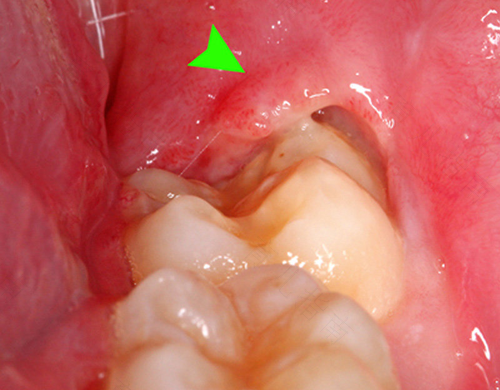

都说聪明的人才会长智齿,长智齿的人聪明不聪明不知道,但是如果智齿长成了阻生齿,就容易塞牙,导致发炎,智齿发炎就需要拔出,否则会给生活带来很多不便,牙痛过的人都知道其中的滋味。那么,拔智齿后疼么?